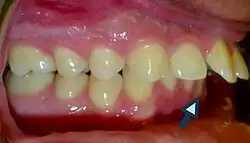

Patients with increased overjet or lip incompetence are also at a higher risk of suffering traumatic injuries in the upper incisors (Schatz et al., 2020).Overjet